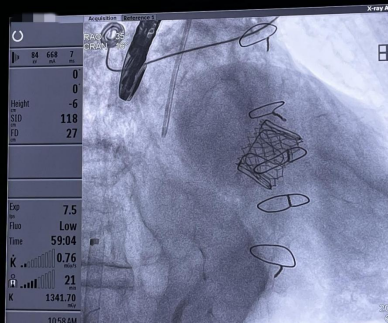

经过术前的身体评估、诊断分析、充分的准备后,手术在心内科导管室里开始。于波教授指导,陈涛副主任医师、张东会副主任医师和杨光副主任医师,在经食管超声引导下,凭借扎实的操作技术、团队默契的配合,建立经股静脉入路穿刺房间隔,在衰败的人工二尖瓣中顺利植入一枚Edwards Sapien 3球扩式瓣膜,成功为陈奶奶完成了经导管二尖瓣置换术后“瓣中瓣“植入术。手术仅用时1小时顺利完成,术后超声评估人工心脏瓣膜功能正常。

顺利植入一枚Edwards Sapien 3球扩式瓣膜